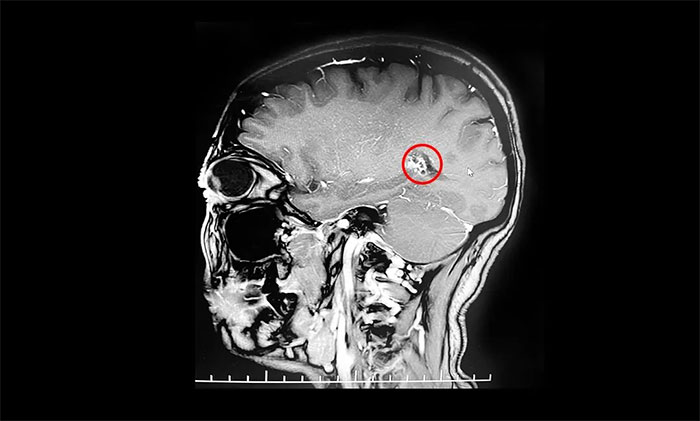

入院后,行海马MRI平扫+MRS+MRSI检查,MRS提示右侧海马Cho峰升高;扫及右侧颞叶深部(侧脑室颞角外下部)见一直径约15mm类圆形异常信号;右侧侧脑室颞角稍宽。患者既往高血压病史4年,曾因右侧颞部海绵状血管瘤致蛛网膜下腔出血2次。杨忠旭教授结合患者症状,病史,磁共振、脑电图等系列检查,考虑海绵状血管瘤及周围皮层为致癫灶。患者已经明确有反复出血史,手术指征明显,需行手术切除治疗,预防再次出血引起神经功能及癫痫等症状。

▲ 海绵状血管瘤